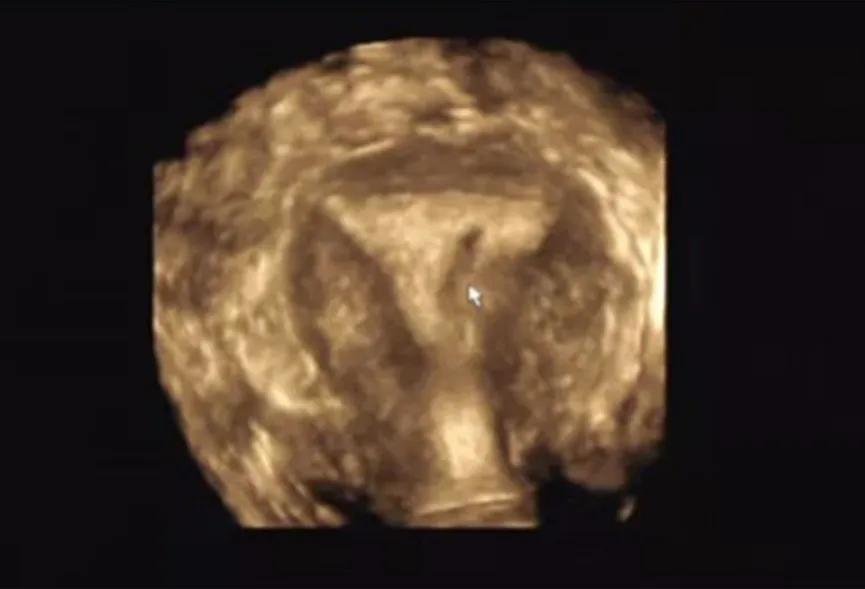

经阴道三维超声检查,一般是在常规阴道超声检查的基础上加做,通俗的理解,就是立体超声。相比常规阴超,三维超声可以全方位,多切面,多角度来观察子宫内膜及宫腔的环境,可以提供更多的诊断信息。其中最有价值的切面就是冠状切面。同时实时三维能够旋转,从每个切面成像,可以准确,迅速的获得丰富立体的子宫内膜完整图像信息,更利于诊断准确性的提高,与传统的子宫输卵管造影比较,具有更好的实用价值,更得到临床工作中的认可。

三维超声表现

当发生宫腔粘连时,中央性粘连表现为内膜的缺损,回声不均匀等,周围性粘连则可能变现为倒三角形结构的破坏,宫底部或双侧壁的不对称,宫角圆顿,宫腔缩窄,内膜及基层分界不清晰,不规整等。